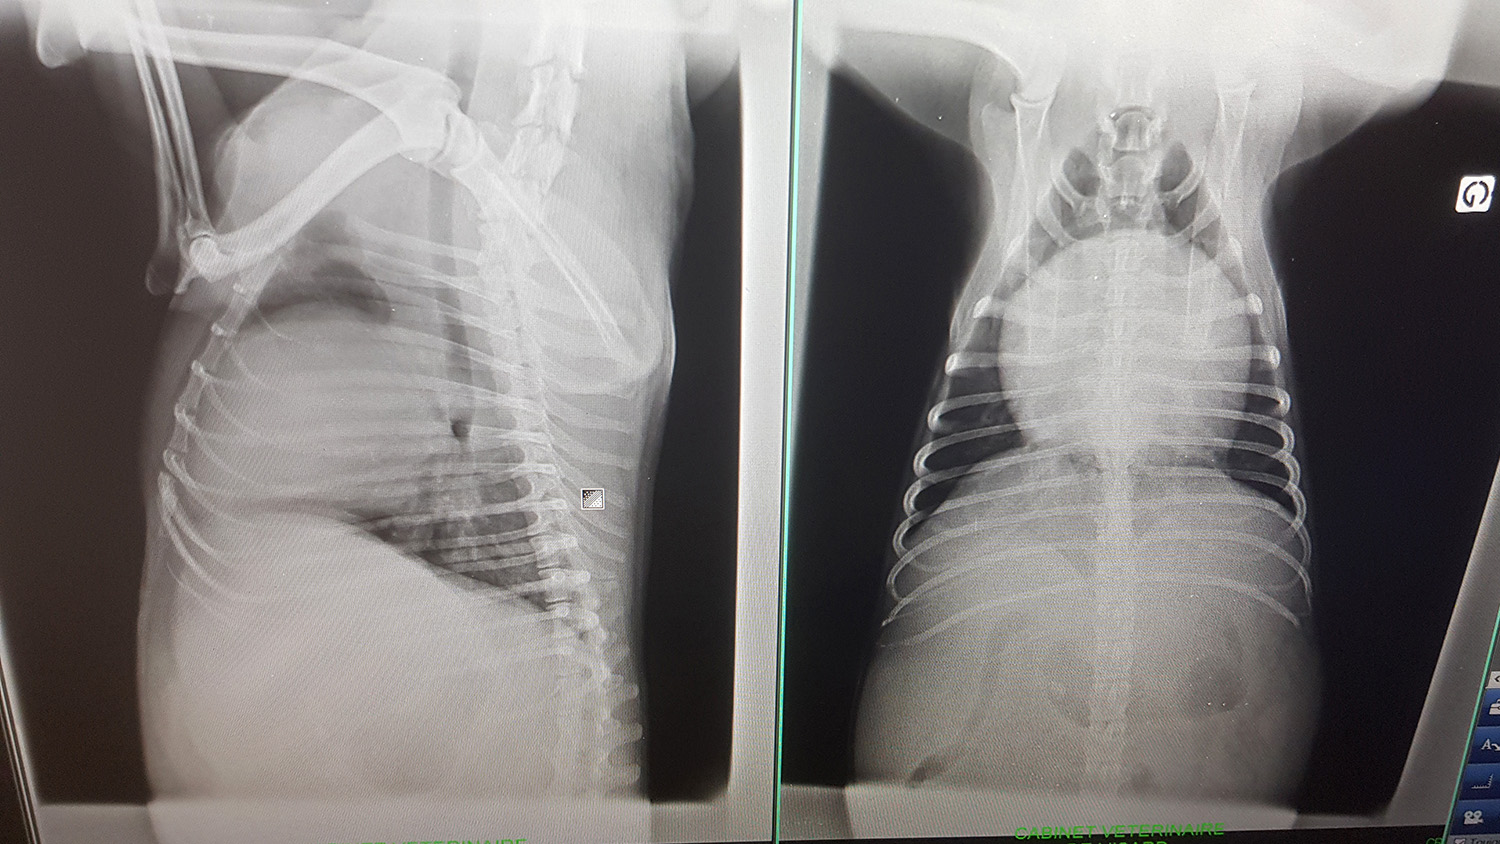

- radiogaphies du thorax : lors d'affections respiratoires, lors d'affections cardiogéniques, lors de bilans d'extensions (dans le cadre de processus tumoraux), etc.

Cardiomégalie (chien)